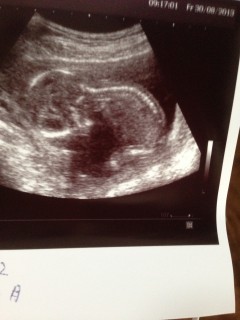

前回11週で49.1mmでした。今回1カ月ぶりの健診でBPD(頭の大きさ)3.5cmで先生に16週の大きさだねと言われました(笑)よく動いててなかなか先生に測らせてあげてない子でした(笑)とても可愛いです。性別は次の健診で分かるだろうと言われました。楽しみです!